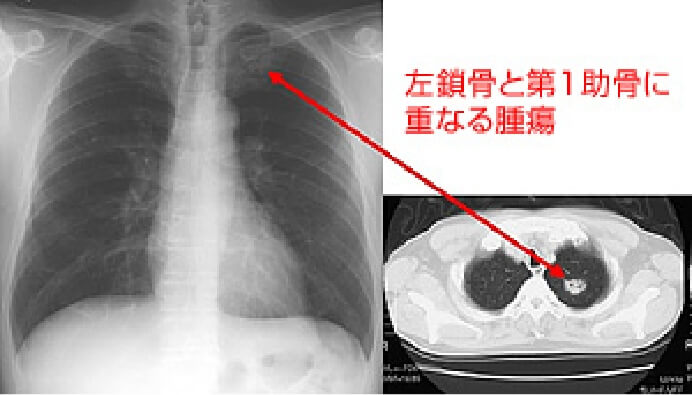

おもに呼吸器(気管・肺など)、循環器(心臓)などに病気があるかどうかを調べるための検査です。肺がん・じん肺・肺結核・肺炎・気胸・胸水・心拡大などの診断に有用です。しかし、小さな肺がんは検出されないことがあるため(症例画像参照)、喀痰細胞診検査・胸部CT検査をあわせておこないます。

肺・気管・気管支などを輪切り(断面)の状態で撮影し、小さい病変を見つける検査です。早期肺がんの診断はもちろんのこと、「低線量CT装置」を用いることにより、X線写真では発見しにくい中心型(肺門型)肺がんも検出することができます。(症例画像参照)

単純X線写真で発見困難な症例1